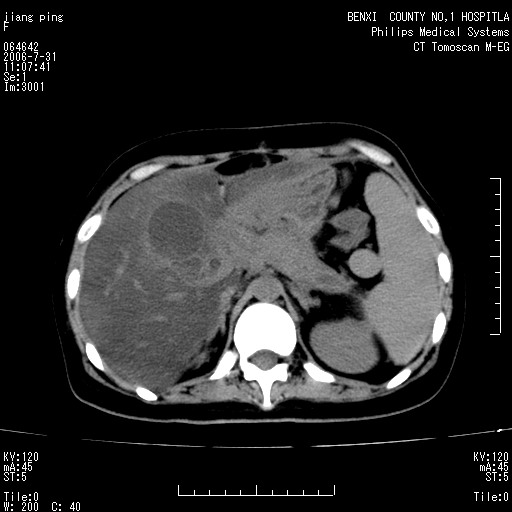

以下是引用晓杰在2006-8-1 9:01:00的发言:[br]支持营养不良导致脂肪肝。[br]胰头增大界限不清,考虑为胰腺炎破坏十二指肠粘膜、肠壁增厚、肠腔狭窄,并与胰头粘连所致

以下是引用jiajie在2006-7-31 20:34:00的发言:[br]支持营养不良导致脂肪肝。[br]胰头增大界限不清,考虑为胰腺炎破坏十二指肠粘膜、肠壁增厚、肠腔狭窄,并与胰头粘连所致。